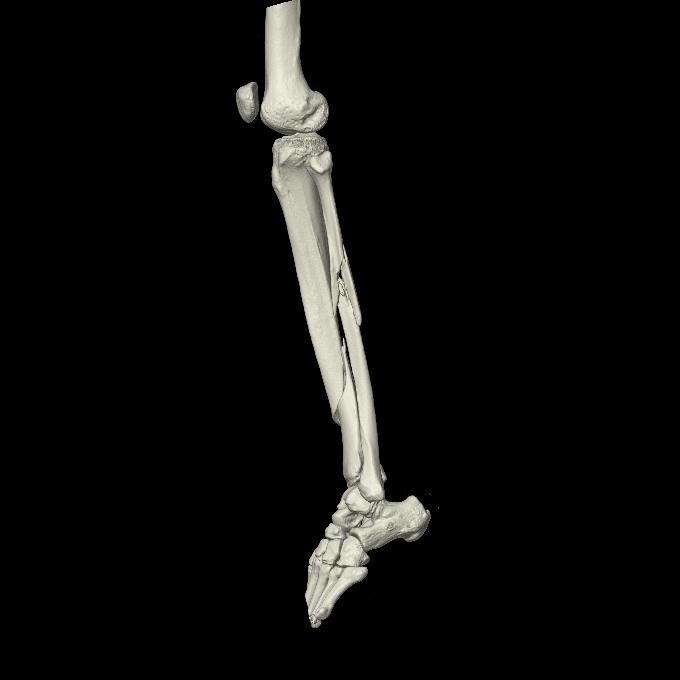

102803 1/12(キウスなし) 1/27 左下腿 4R 30歳女性 左脛骨軸内釘